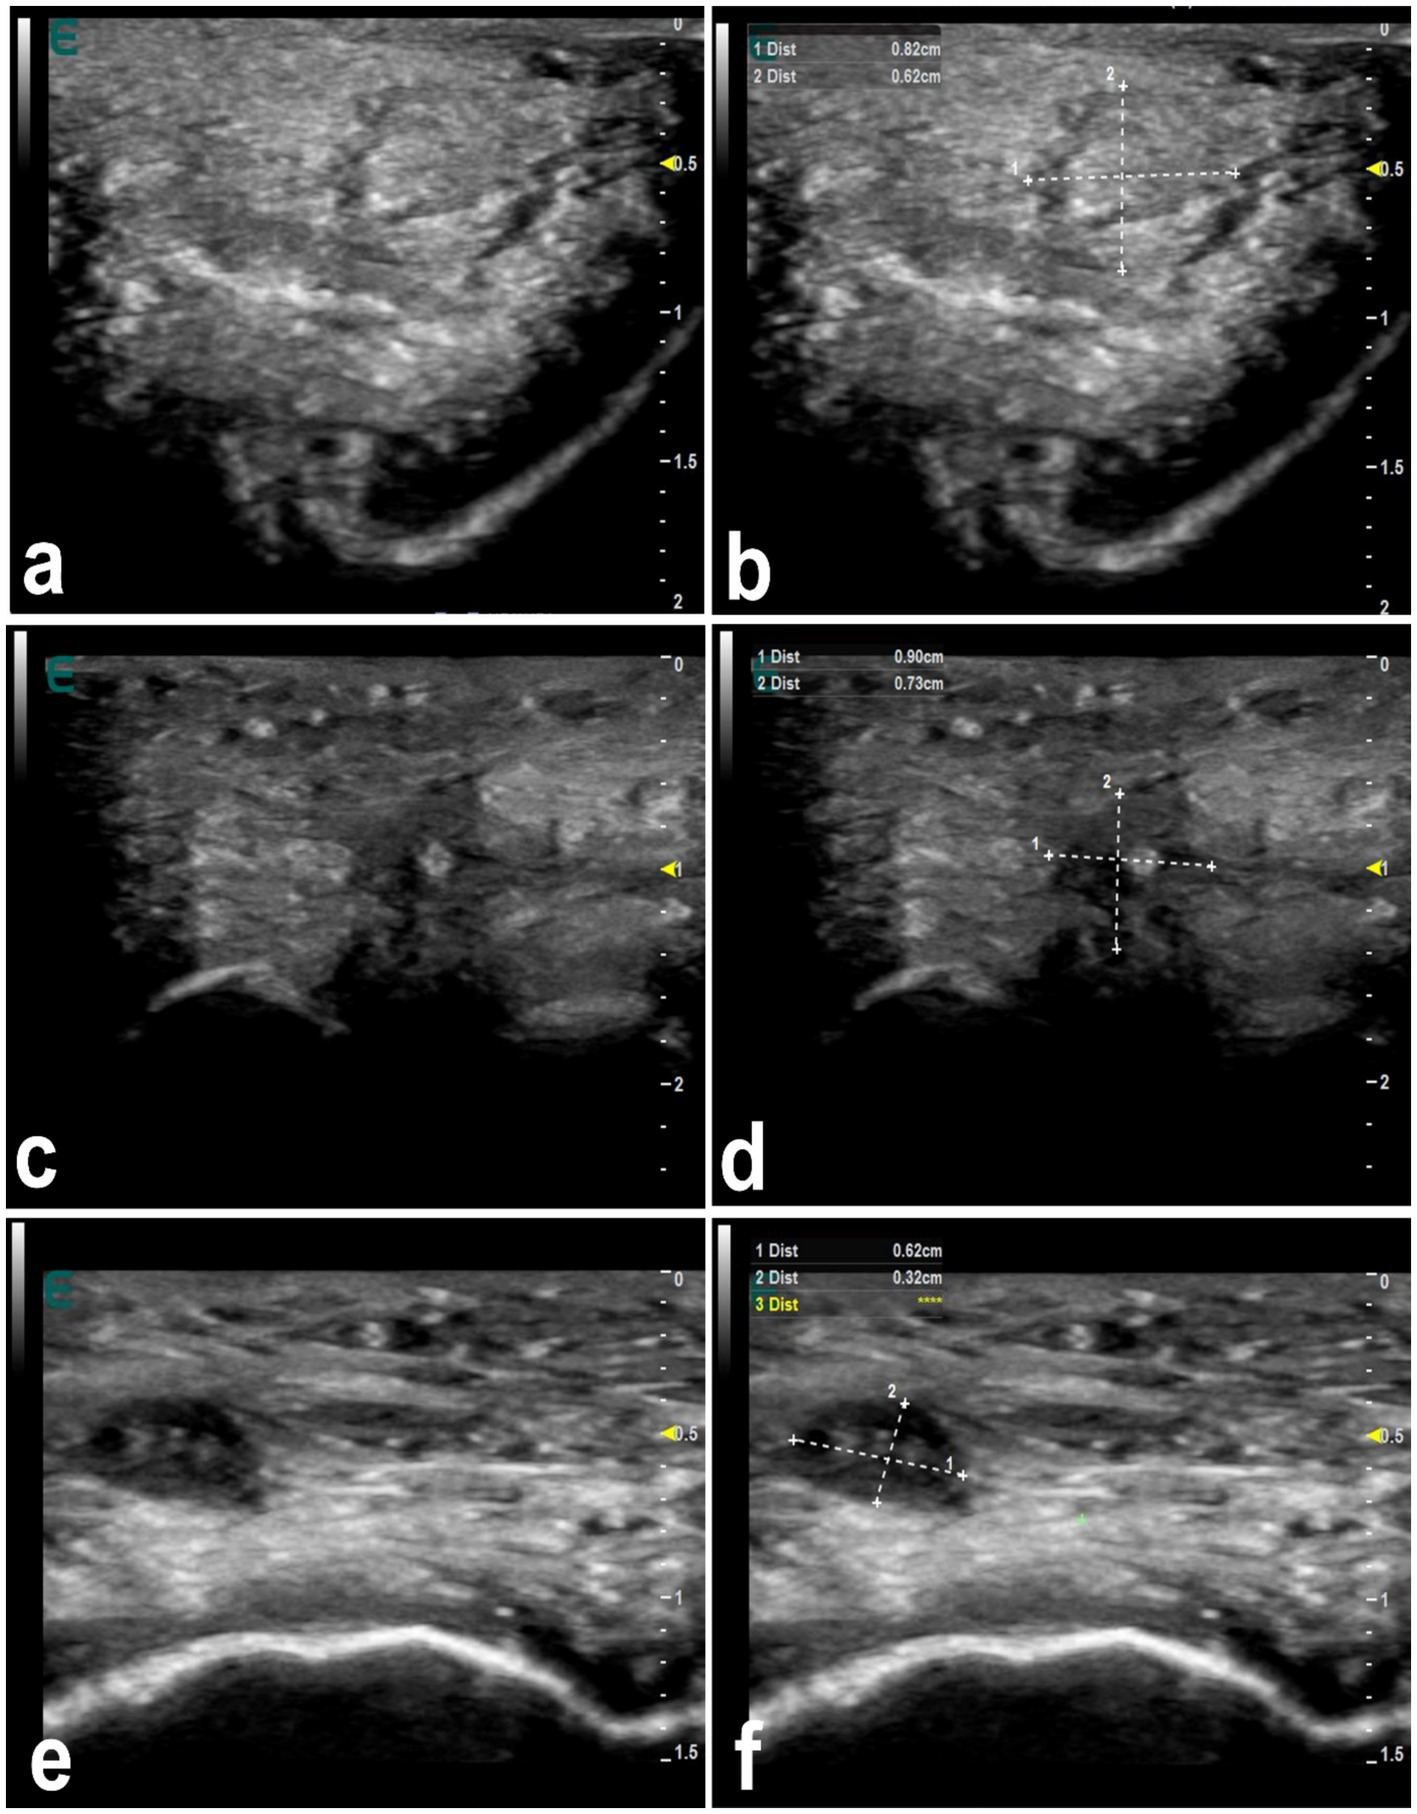

Figure 5 shows mapping of the lips in a healthy camel showing different locations where injected filler materials are commonly injected. In healthy camels, the dermis appears hyperechoic, contrasting with the hypoechoic subcutaneous tissue (16). Filler substances, even those approved by regulatory agencies, can cause in humans detectable changes in tissue structure (63). Injected fillers in dromedary camels typically appear as anechoic or hypoechoic areas on ultrasound, presenting as single or multiple deposits of varying size. In affected camels, the boundary between the dermis and subcutaneous tissue becomes indistinct (Figure 6). Fillers in the firm edges of the lips exhibit hypoechoic signals, with the overall sonographic pattern of injected lips appearing heterogeneous (Figure 7). Lip nodules are visualized as either isoechoic structures with a hypoechoic rim or as hypoechoic lesions with an echogenic center (Figure 8).

Ultrasonographic appearance of injected fillers in the upper lip of 3 female dromedary camels (a,c,e). The injected filler appears anechoic to hypoechoic and was imaged in the form of small or large, single or multiple deposits. It is difficult to distinguish the subcutaneous tissue from the dermis. Images (b,d,f) represent a schematic representation of the images (a,c,e), respectively [Reproduced from (44)].

Figure 7

Ultrasonographic features of hardened tip of the lips in 3 dromedary camels with injected fillers (a,c,e). The injected filler appears hypoechoic and the scanning patterns of the injected lips appear heterogeneous. Images (b,d,f) represent a schematic representation of the images (a,c,e), respectively [Reproduced from (44)].

Figure 8

Ultrasonographic features of lip nodules in 3 camels as a result of filler injections (a,c,e). They appear as either isoechoic with a hypoechoic rim or hypoechoic with an echogenic center. Images (b,d,f) represent a schematic representation of the images (a,c,e), respectively [Reproduced from (44)].